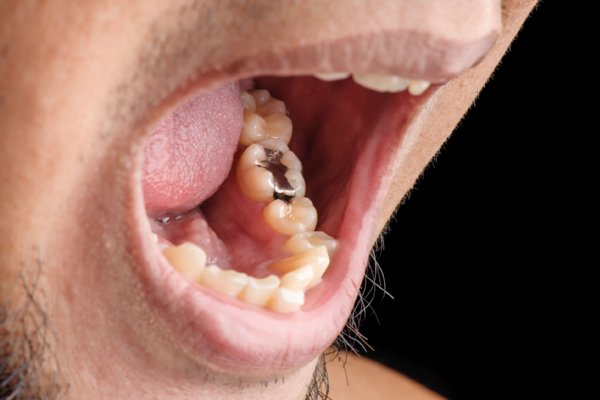

女だけど歯を磨かなかった結果wwwwwwwwwwww ミラクルミルク